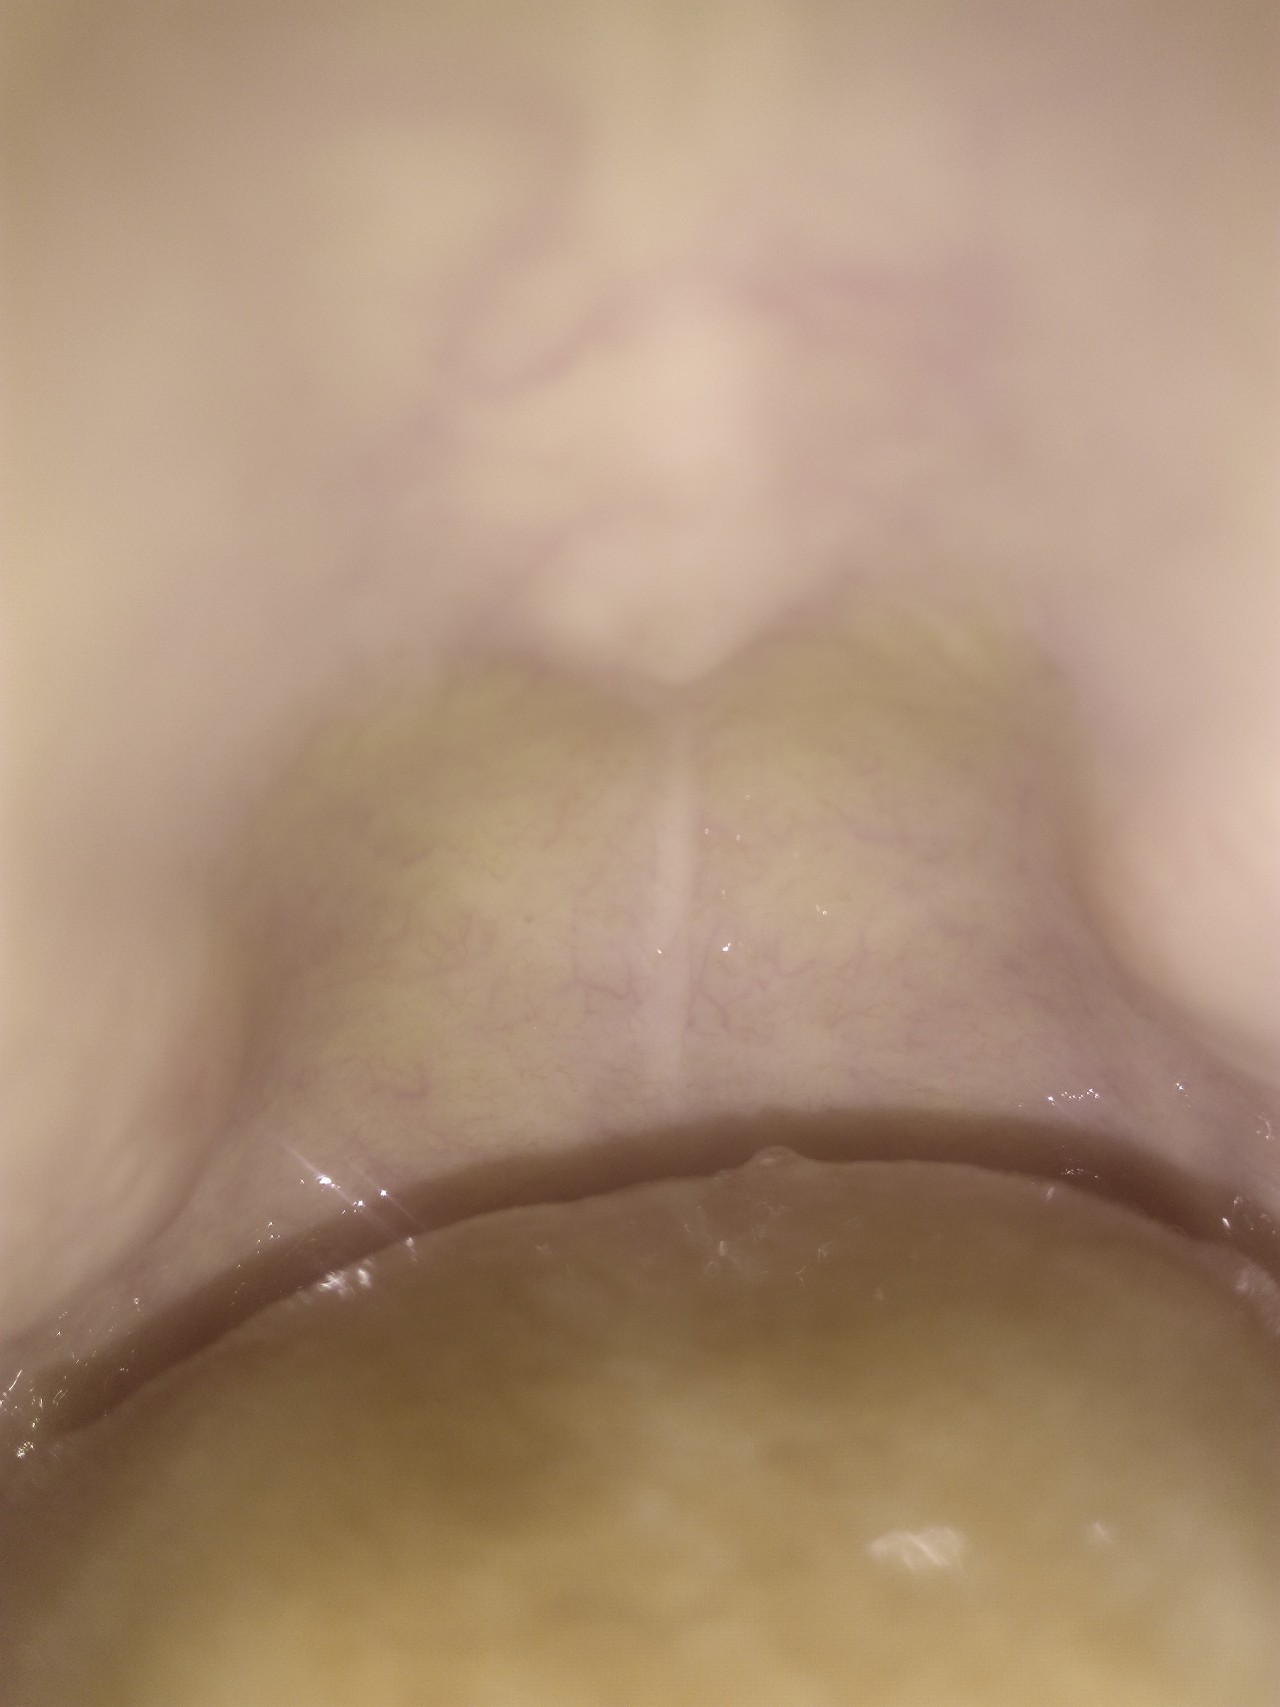

Здравствуйте, у меня вот такая проблема недавно появилась шишка на нёбе я ее заметила когда была температура кашель горло было красное язык белый все симптомы прошли а шишка осталась пока в больницу не могу пойти. Еще перед этим я сьела много конфет леденцов. Что это может быть?

Таким образом, скорее всего, отреагировали малые слюнные железы слизистой оболочки неба на избыточный контакт с леденцами. На данный момент все должно пройти или значительно уменьшится. Отпишитесь о результатах.

Последующие приемы леденцов могут приводить к рецидивам. Употребляйте в пищу другие сладости, не требующие активного воздействия на твердое небо. В течение недели должно еще уменьшиться, но может остаться ощущаемая безболезненная «горошинка».

Опасного ничего нет. Так реагирует малая слюнная железа. Как будет возможность, за очной консультацией обращайтесь к хирургу-стоматологу.